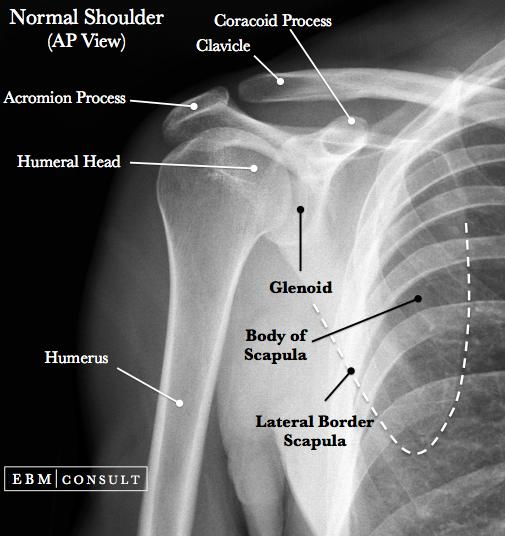

Shoulder X-ray

Normal views: AP and Lateral Y view (most common)

AP view and Lateral Y view are the most commonly used.

AP View